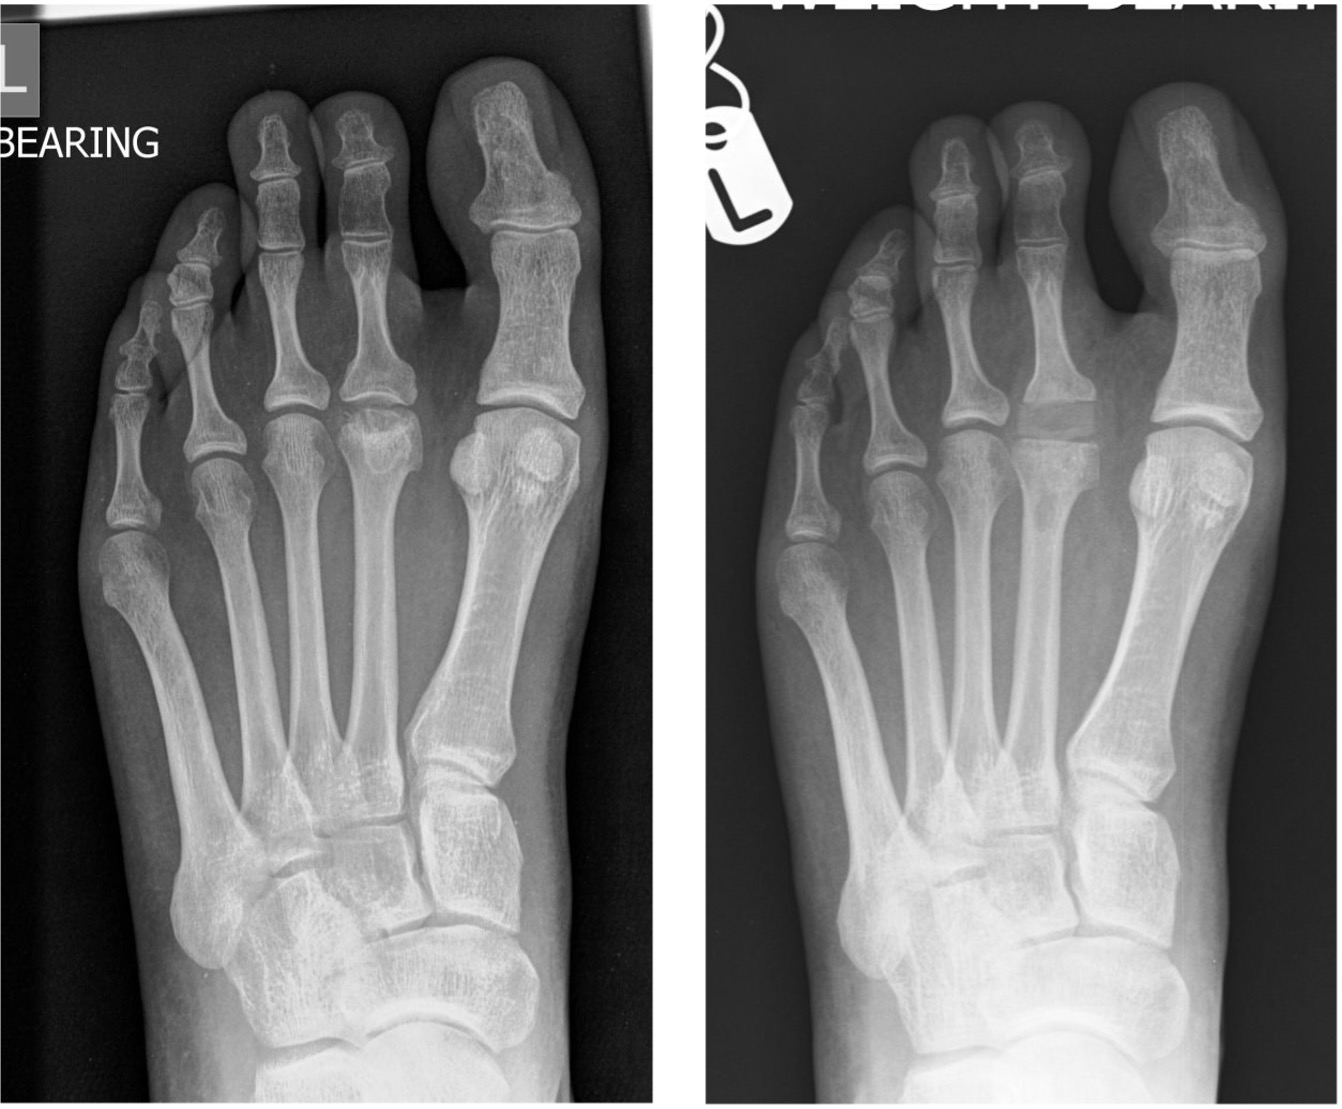

- anatomic anomaly e.g. relatively long 2nd MT compared to the 1st MT (Figure 1)

Figure 1: DP radiographic view of a long 2nd metatarsal

Plain standing radiographs offer a clear diagnosis in established cases (Figure 3).